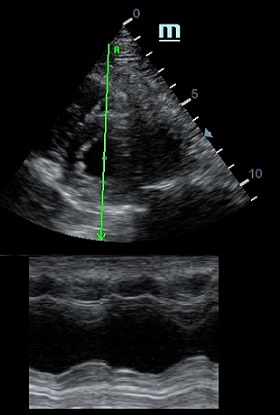

MAPSE - амплитуда движения латерального кольца митрального клапана, позволяет рассчитать фракцию выброса по формуле EF = 4.8 × MAPSE (mm) + 5.8, очень быстрый и гораздо более точный («прародитель Strain») метод чем широко распространенный метод Teicholtz. В современных приборах можно легко добавить свою формулу при отсутствии ее в стандартном калькуляторе. Главным условием является проведение линии М-режима параллельно стенке левого желудочка в апикальном четырехкамерном сечении, что легко достигается при использовании функции Free Xros.